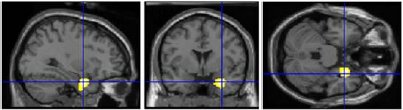

1) canonical sculptures activated right insula (mediates emotions; connects to/from amygdala): evidence for _________ beauty (“I can see why people like that.”)

right insula activity